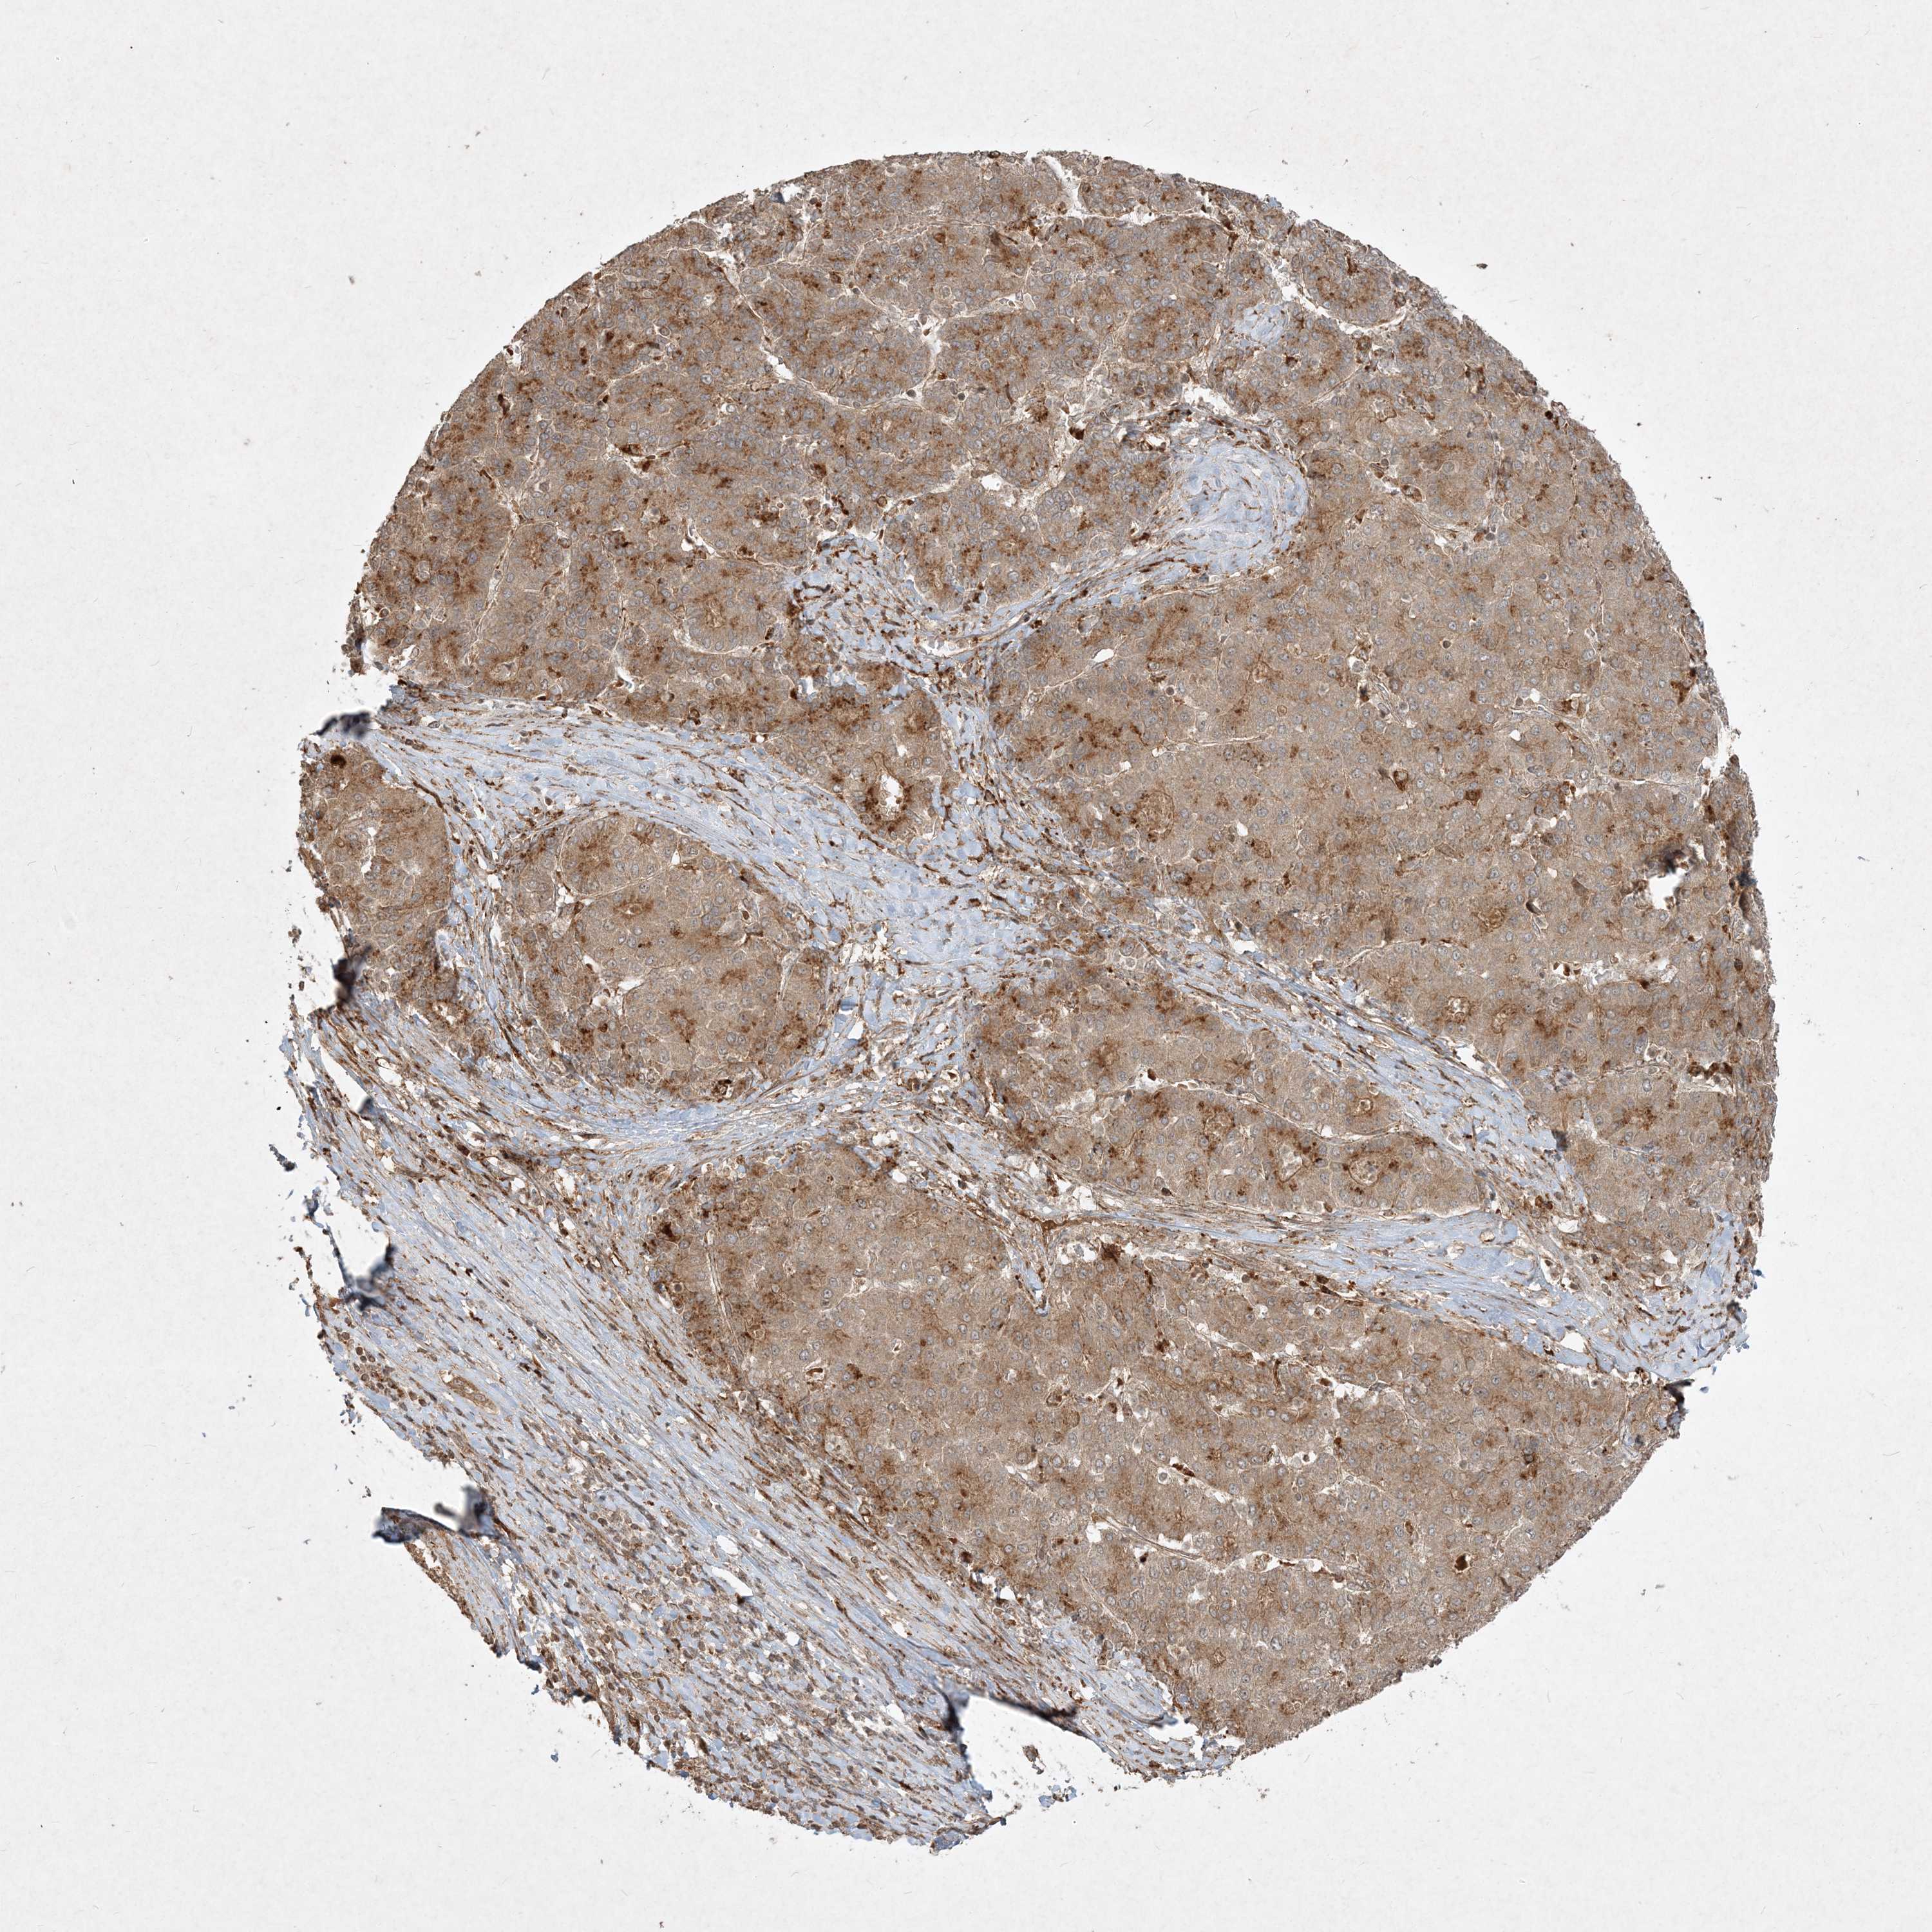

LIVER CANCER - Protein expressioni

A mouse-over function shows sample information and annotation data. Click on an image to view it in a full screen mode. Samples can be filtered based on level of antibody staining by selecting one or several of the following categories: high, medium, low and not detected. The assay and annotation is described here.

Note that samples used for immunohistochemistry by the Human Protein Atlas do not correspond to samples in the TCGA dataset.

Antibody stainingi

Antibody staining in the annotated cell types in the current human tissue is reported as not detected, low, medium, or high, based on conventional immunohistochemistry profiling in selected tissues. This score is based on the combination of the staining intensity and fraction of stained cells.

Each image is clickable and will lead to virtual microscopy that enables deeper exploration of all samples and also displays staining intensity scores, fraction scores and subcellular localization as well as patient and tissue information for each sample.

Antibody HPA040017

Antibody CAB034257

Staining

High

Medium

Low

Not detected

Intensity

Strong

Moderate

Weak

Negative

Quantity

>75%

75%-25%

<25%

None

Location

Nuclear

Cytoplasmic/membranous

Cytoplasmic/membranous,nuclear

Cholangiocarcinoma

Carcinoma, Hepatocellular, NOS